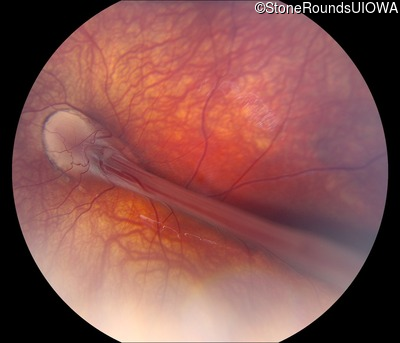

Visit at age: 6 years

Fundus Photography - Right - 20/300

Exemplar